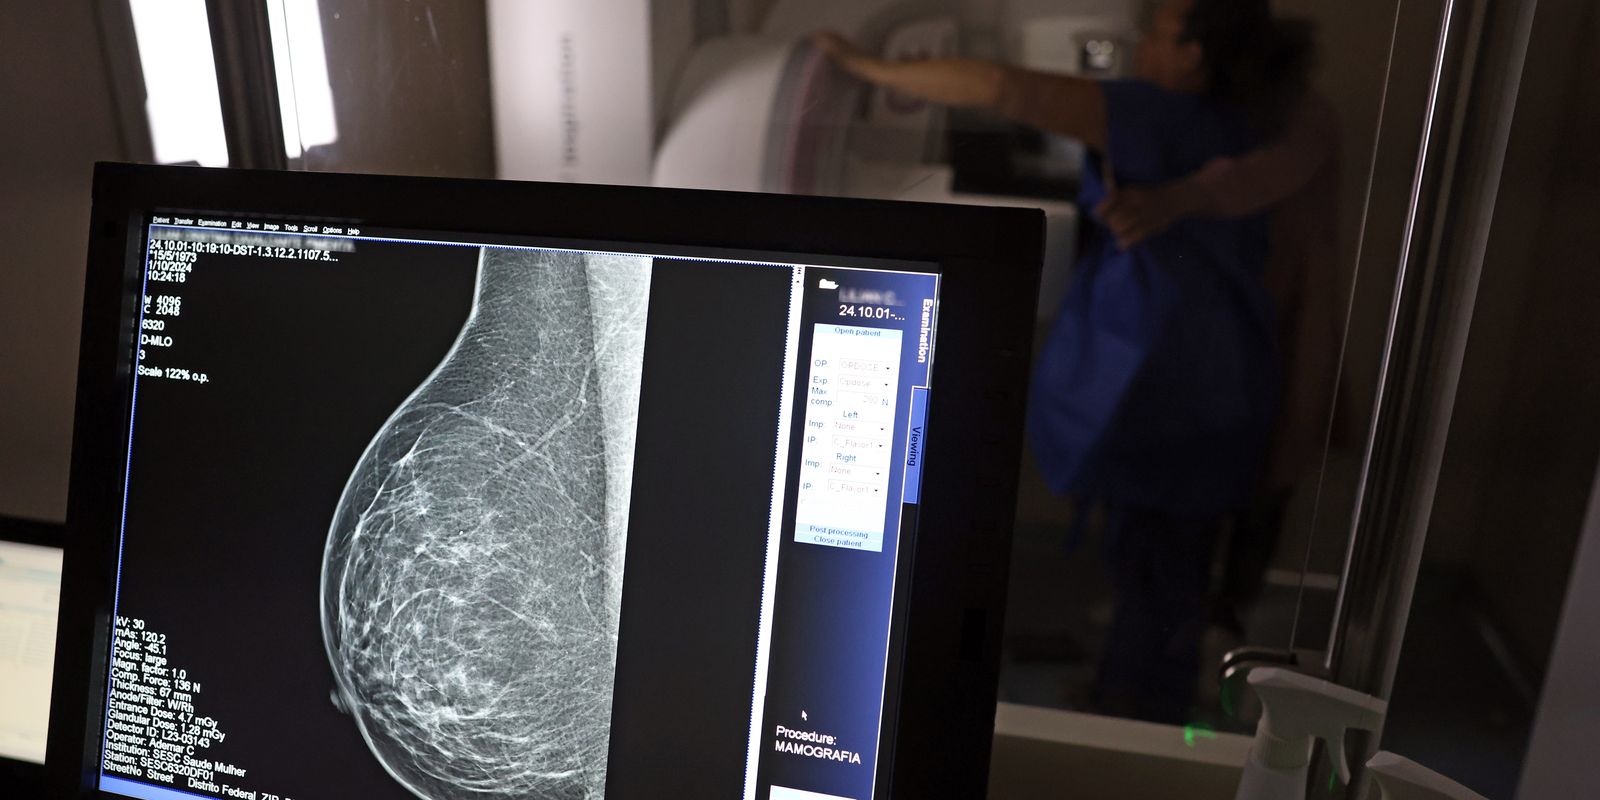

No mês de conscientização sobre o câncer de mama, um relatório destaca a importância de acesso igualitário ao rastreamento e tratamento da doença. Segundo o Atlas da Radiologia no Brasil, do Colégio Brasileiro de Radiologia e Diagnóstico por Imagem (CBR), o acesso aos mamógrafos ainda é um desafio.

Em setembro, o Ministério da Saúde ampliou as diretrizes de rastreamento, recomendando que mulheres entre 40 e 49 anos realizem mamografias, mesmo sem sintomas. De acordo com o Instituto Nacional do Câncer (Imca), mais de 73 mil mulheres recebem o diagnóstico de câncer de mama anualmente no Brasil.

“O que é efetivo na redução da mortalidade é você descobrir o tumor antes de ter sintoma clínico. Quanto menor o tumor, melhor para a gente descobrir o tratamento e maior a chance de cura. E a gente só consegue fazer isso com exames de imagem”, diz Ivie.

Ela explica que no caso de diagnóstico de um câncer de mama com menos de 1 cm, a chance de cura é de 95% em cinco anos, independentemente se ele é do tipo mais agressivo. “E esses tumores só vão ser detectados na mamografia. Essas pessoas que têm que ir fazer mamografia são mulheres saudáveis. Não são mulheres doentes”, acrescenta.